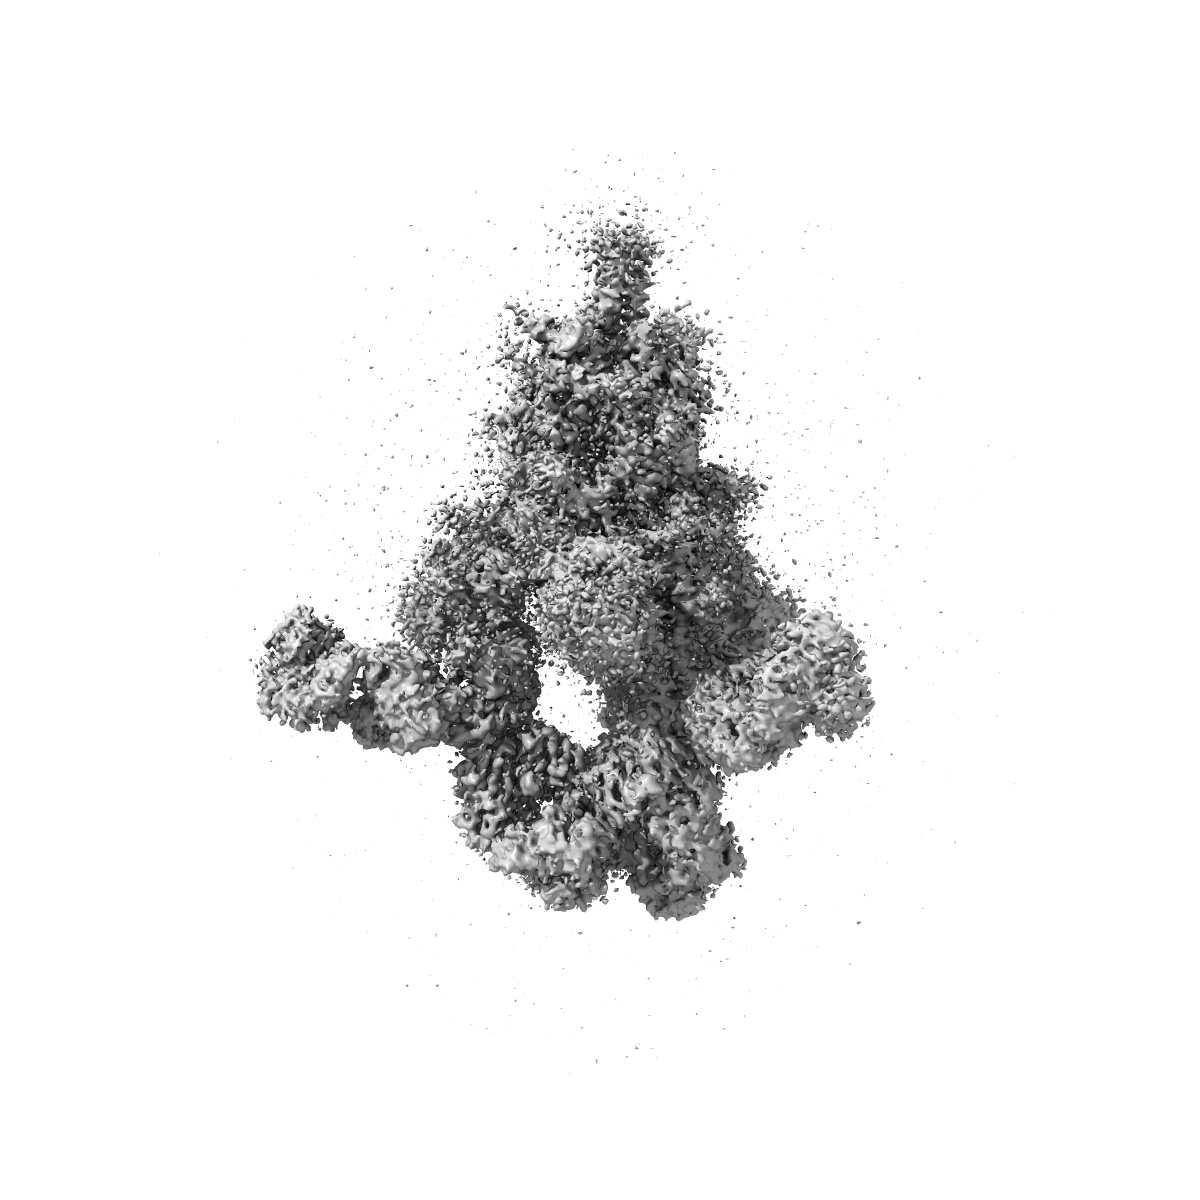

Cryo-EM structure of SARS-CoV-2 Delta Spike protein in complex with BA7054 and BA7125 fab

Single-particle3.2 Å

Sample: Cryo-EM structure of SARS-CoV-2 Delta Spike protein in complex with BA7054 and BA7125 fab